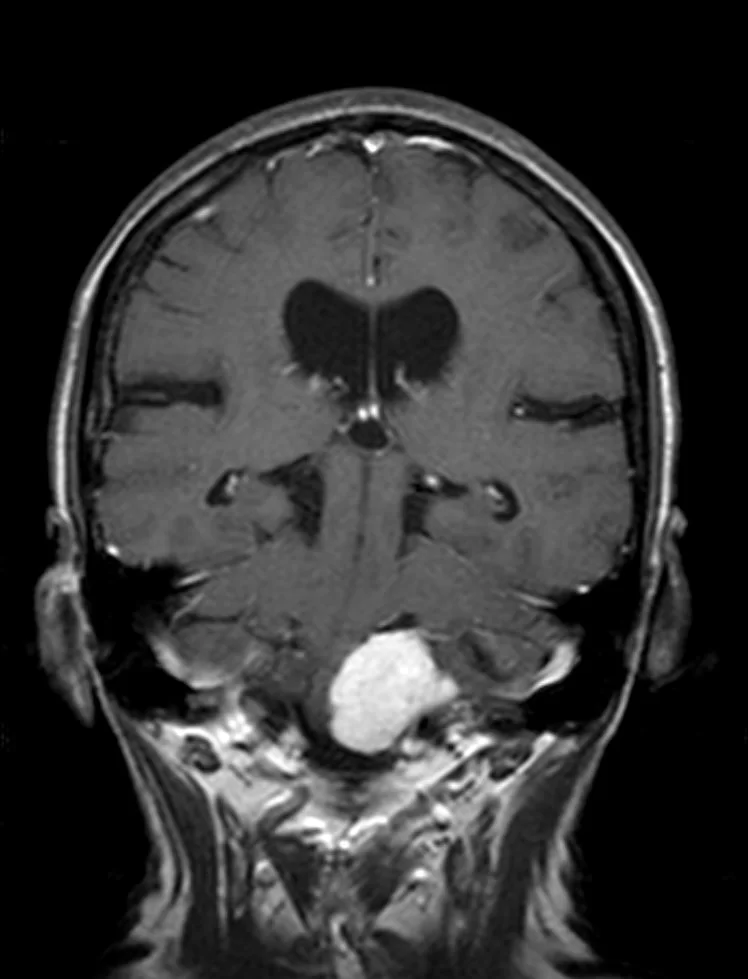

Η μετεγχειρητική μαγνητική τομογραφία εγκεφάλου δείχνει ένα εξαιρετικό αποτέλεσμα, με πλήρη αφαίρεση της βλάβης. Η ιστολογική εξέταση επιβεβαίωσε τη διάγνωση (μηνιγγίωμα WHO I).

Η ασθενής ανάρρωσε άμεσα και πλήρως, χωρίς νευρολογικό έλλειμα και εξήλθε του νοσοκομείου την 7η μετεγχειρητική ημέρα.

Η μετεγχειρητική εικόνα της ασθενούς ήταν εξαιρετική, χωρίς κανένα νευρολογικό έλλειμα από τις εγκεφαλικές συζυγίες (εγκεφαλικά νεύρα) παρά τη θέση και την έκταση του μηνιγγιώματος.